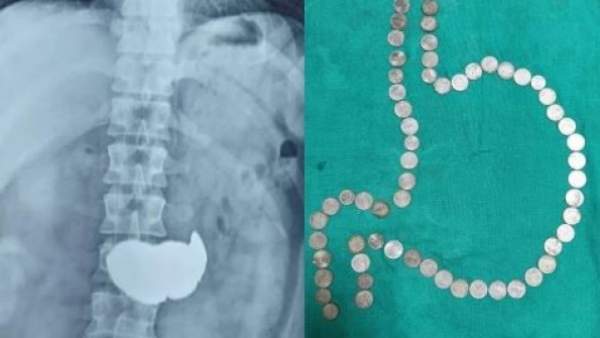

'இளைஞரின் வயிற்றுக்குள் 63 ஒரு ரூபாய் நாணயங்கள்'. . மிரண்டுபோன டாக்டர். . ராஜஸ்தானில் சம்பவம்!

ஜெய்ப்பூர்: ராஜஸ்தான் மாநிலத்தில் வலியால் துடித்த இளைஞரின் வயிற்றில் இருந்து 63 ஒரு ரூயாய் நாணயங்கள் எடுக்கப்பட்டுள்ளது. இவருக்கு சிகிச்சை அளித்த டாக்டர் இதைப்பார்த்து மிரண்டு போனார்.

இதன்படி, இளைஞருக்கு ஸ்கேன் பரிசோதனை செய்யப்பட்டது. தொடர்ந்து ஸ்கேன் முடிவுகளை ஆய்வு செய்த மருத்துவர்களுக்கு வயிறு முழுவதும் எதோ உலோக கட்டி போன்று தென்பட்டது. இதனால், அதிர்ச்சி அடைந்த மருத்துவர்கள் இதுபற்றி இளைஞரிடம் கேட்டனர். இதற்கு பதிலளித்த இளைஞர், மன உளைச்சலால் ஒரு 10 முதல் 15 ஒரு ரூபாய் நாணயங்களை விழுங்கி விட்டதாக கூறினார். இளைஞரின் பதிலை கேட்டு திகைத்து போன மருத்துவர்கள், அறுவை சிகிச்சையின்றி நாணயங்களை எடுத்து விடலாமா? என்பது குறித்து ஆலோசித்தனர். இதற்கு பிற மருத்துவர்களும் ஒப்புக்கொண்டதால் இளைஞரின் வயிற்றில் உள்ள நாணயங்கள் எண்டோஸ்கோபி முறையில் எடுக்க முடிவு செய்யப்பட்டது. இதன்படி, எண்டோஸ்கோபி முறையில், நாணயங்கள் எடுக்கப்பட்டன. இந்த சிகிச்சை இரண்டு நாள் வரை நீடித்தது.

63 நாணயங்கள் எடுக்கப்பட்டன

இது குறித்து மருத்துவர்கள் கூறுகையில், "36-வயது இளைஞர் கடுமையான வயிற்றுவலி எனகூறி மருத்துவமனையில் சேர்ந்தார். அவருக்கு ஸ்கேன் செய்ததில் நாணயங்களை விழுங்கியிருப்பது தெரியவந்தது. இதையடுத்து, இளைஞருக்கு சிகிச்சையை மேற்கொண்டோம். இரண்டு நாட்கள் நீடித்த சிகிச்சைக்குப் பிறகு இளைஞரின் வயிற்றில் இருந்து 63 நாணயங்கள் எடுக்கப்பட்டன. இளைஞர் வெறும் 10 முதல் 15 நாணயங்களே விழுங்கியதாக கூறினார். ஆனால் உண்மையில் அவர் 63 நாணயங்களை விழுங்கி இருந்து இருக்கிறார். அனைத்தும் ஒரு ரூபாய் நாணயங்களாக இருந்தன.